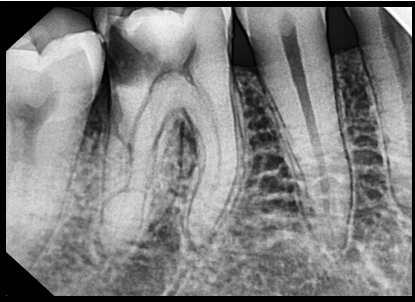

위 치아를 보시면 치아가 손상되어 신경까지 침범한걸 보실 수 있습니다. 이렇게 이미 신경이 손상된 경우, 신경치료가 필요합니다. (출처: https://www.researchgate.net)